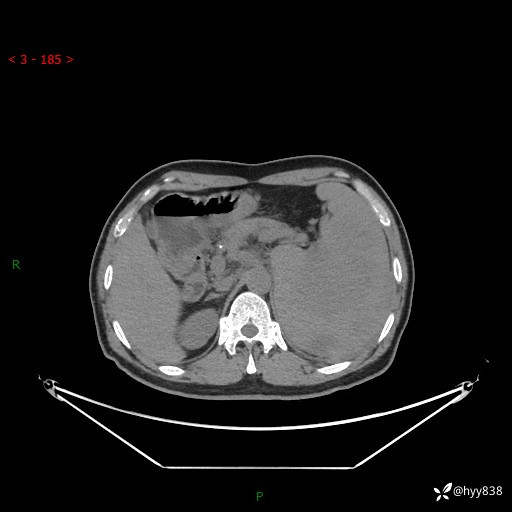

现病史:患者自诉2024年2月无明显诱因下出现剑突下隐痛,进食后加重,伴腹胀、夜间盗汗,当时无畏寒、发热、胸闷、胸痛、气促、恶心、呕吐、腹泻、皮肤巩膜黄染,自行口服布洛芬片1片止痛治疗(口服20余天)后腹痛减轻。后腹胀逐渐加重,4月12日患者早餐时突然出现剑突下剧烈疼痛,放射至后背,伴恶心、呕吐、大汗淋漓、呼吸困难,呕吐为胃内容物,无畏寒、寒战、发热、头晕、头痛、胸闷、胸痛、意识丧失,遂立即至当地第五人民医院住院,心电图、心肌酶未见明显异常,腹部CT示脾脏占位性病变、腹膜后淋巴结增大,予抗感染、解痉止痛等对症治疗,仍有明显腹胀。现为求进一步诊治前来我院门诊就诊,拟“脾脏占位?”收入我科。 自起病,患者食欲差,精神、睡眠可,二便正常,体重下降3kg左右。

上腹部CT平扫

增强(动脉期+静脉期)